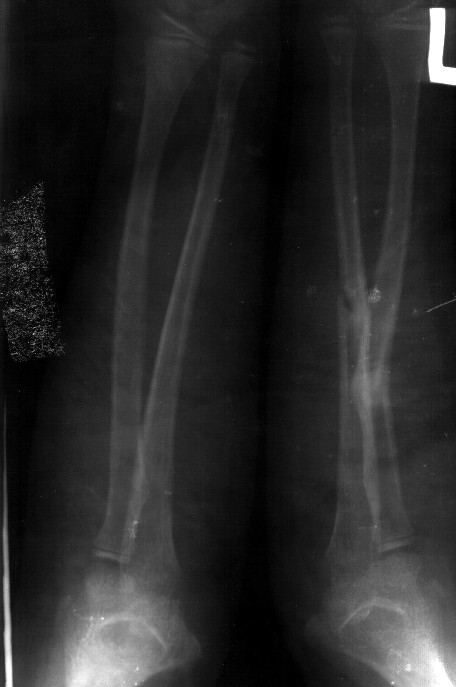

Re: Консолидированный перелом костей предплечья

Сделал симметричные снимки с максимальной супинацией и пронацией при согнутом предплечье в 90 град. Объем ротационных движений 90-100 град.